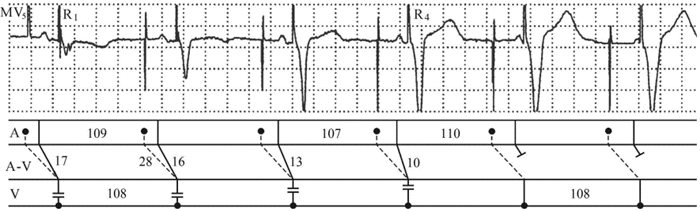

病例1:患者女性,73岁,临床诊断:病态窦房结综合征、植入双腔起搏器(SJM XLDR 5356型)1年。设置的起搏器参数:基本起搏周期1080 ms,频率56~125次/min,A-V间期280 ms,心房不应期300 ms,心室不应期400 ms。MV5(图 1)显示窦性P-P间期1.07~1.10 s,频率55~56次/min;双腔起搏器的起搏周期1.08 s,频率56次/min,A-V间期0.28 s;心房起搏脉冲与其后P波的时距即A-P间期由0.11 s→0.13 s→0.16 s→0.17 s→0.21 s→0.23 s逐渐延长,表明该P波不是由心房起搏脉冲所引发,而是为窦性P波,显示心房脉冲未能夺获心房,至于起搏器未能感知窦性P波,与窦性P波落在心房感知器的不应期内或心房电极脱位有关;P-V间期由0.17 s→0.16 s→0.13 s→0.10 s→0.08 s→0.05 s逐渐缩短,相应的QRS′波群逐渐宽大畸形,其中R1~R4搏动为不同程度的室性融合波,系窦性激动经房室交接区下传与经A-V通道起搏心室所形成的室性融合波。心电图诊断: ①窦性心动过缓;②双腔起搏器,心房起搏功能异常而感知功能难以评价;③心室起搏功能正常而感知功能无法评价;④不同程度的室性融合波引发起搏QRS′波形多变;⑤需结合临床或程控诊除心房电极有无脱位或起搏阈值增高(后经临床证实是心房电极脱位所致)。

梯形图解中A行中“实心圆点加虚线”代表起搏器节律,实线为窦性节律;A-V行中虚线为经人工设置的A-V通道下传心室,实线为窦性激动经房室结通道下传心室,以下同。 图 1 双腔起搏器出现不同程度的室性融合波引发起搏QRS′波形多变

不同程度的室性融合波。起搏器发放的冲动与自身节律发放的冲动各自控制一部分心室肌而形成室性融合波,视其融合程度不同,起搏 QRS′波形可以多变(图 1)。